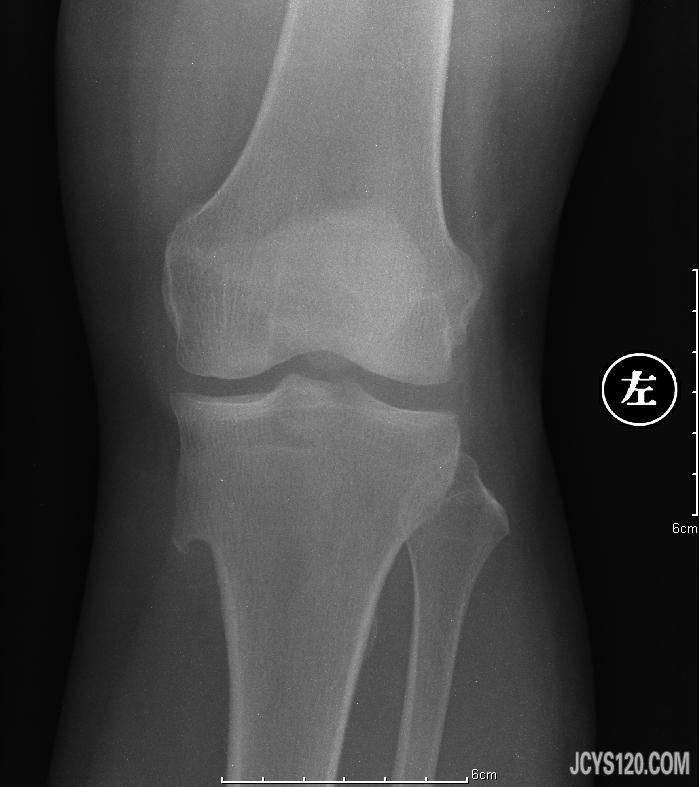

患者女,52岁,膝关节疼痛。 阅读全文>

患者女52岁,主诉膝关节周围疼痛,今天在县医院拍的片子。 阅读全文>